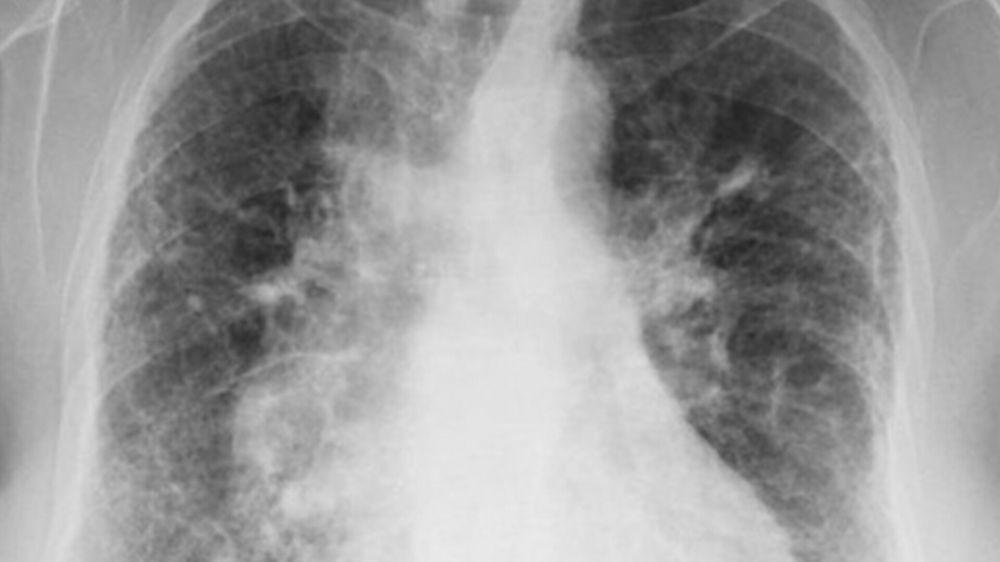

Questa condizione rientra nel vasto gruppo delle malattie polmonari interstiziali, note come ILD, dove il vero problema risiede nell’infiammazione o nel danno all’interstizio polmonare, un tessuto cruciale per la respirazione. Quando questa struttura è compromessa, lo scambio di ossigeno nei polmoni risulta gravemente compromesso.

Quello che veniva percepito come un semplice affanno si è rivelato un progressivo saccheggio dell’ossigeno vitale. Nel tessuto che circonda gli alveoli, lo spazio polmonare conosciuto come interstizio, qualcosa aveva innescato un danno infiammatorio che interferiva con ogni scambio respiratorio. Di colpo, a rendere il quadro ancora più allarmante è stata la rapidità con cui la situazione è degenerata, portando l’artista a un ricovero urgente. Qual è stato l’esito di questa violenta accelerazione del male?